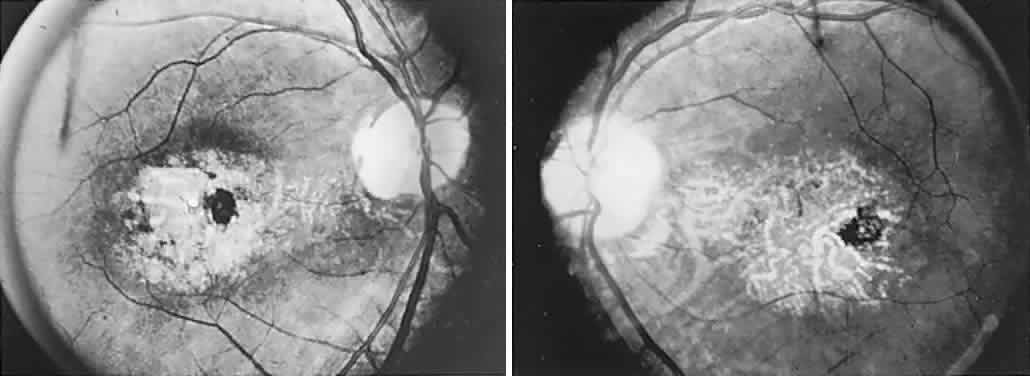

The retinal variety may be admixed in a person who suffers the more conventional attacks of migraine. It is presumed that vasospasm in the retinal circulation determines transient hypoxia, perhaps somewhat similar to the visual cortical event. On rare occasions, the fundus has been examined during typical retinal migraine episodes, and arterial constriction has been described. Wolter and Burchfield106 photographically documented such an episode and demonstrated mild “retinal edema”; vessel narrowing is also evident (Fig. 8). Fortunately, permanent complications of retinal migraine are rare. These may take the form of central retinal artery occlusion or ischemic papillopathy (see Volume 2, Chapter 16); nerve fiber bundle visual field defects may be demonstrated (Fig. 9).

Fig. 8. Retinal migraine. A. During amaurotic episode. Note the dusky appearance of the fundus, increased retinal sheen (possibly edema), and dark narrowed veins (arrows). The disc is also hyperemic. B. Fundus after episode. Compare paired arrows. (Courtesy of Dr. J. Reimer Wolter)